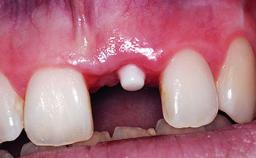

A 32-year-old female Caucasian patient with a compromised maxillary right central incisor was referred to us by a general dentist. Her chief complaints were discomfort and mobility of tooth 11 with unsatisfactory esthetics due to discoloration. The patient reported a previous trauma, some years earlier, as the origin of pathology on the afflicted tooth. Anamnesis was negative for any other dental or periodontal pathology in the remaining dentition. The patient did not take any medication and reported to be a light smoker (5–10 cigs/day). She had high esthetic expectations of her treatment. The extraoral examination revealed a high smile line with full exposure of her maxillary teeth and surrounding soft tissue in the area between the second premolars.